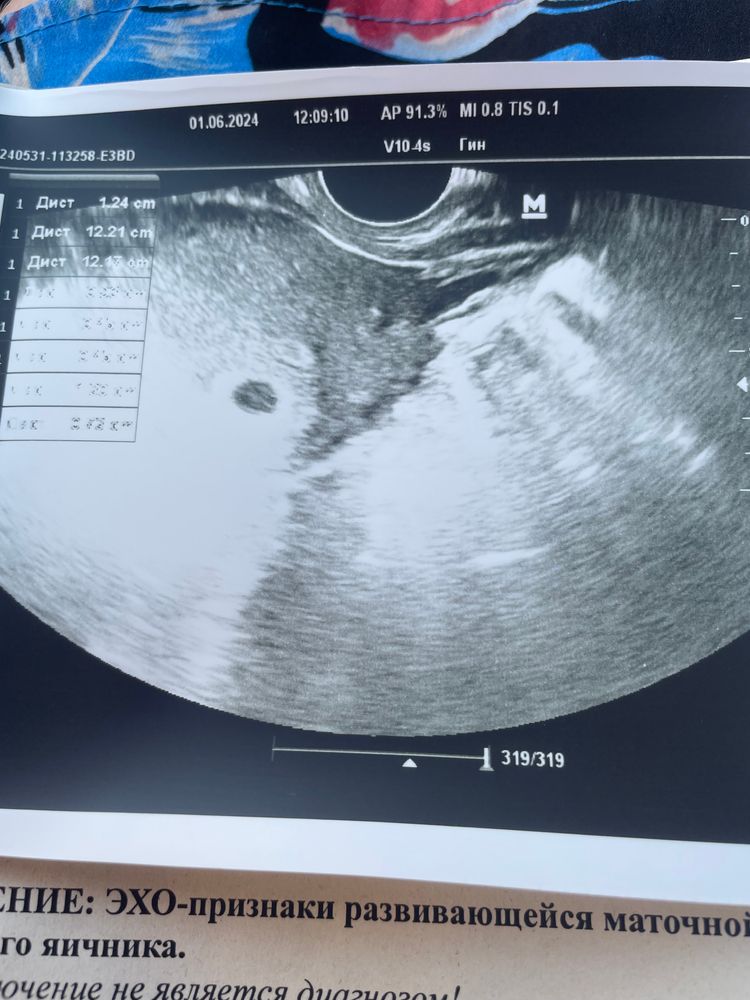

22 дпо или 5 день задержки узи

Плодное яйцо-4 мм

срок 4-5 недель🌺🌺🌺